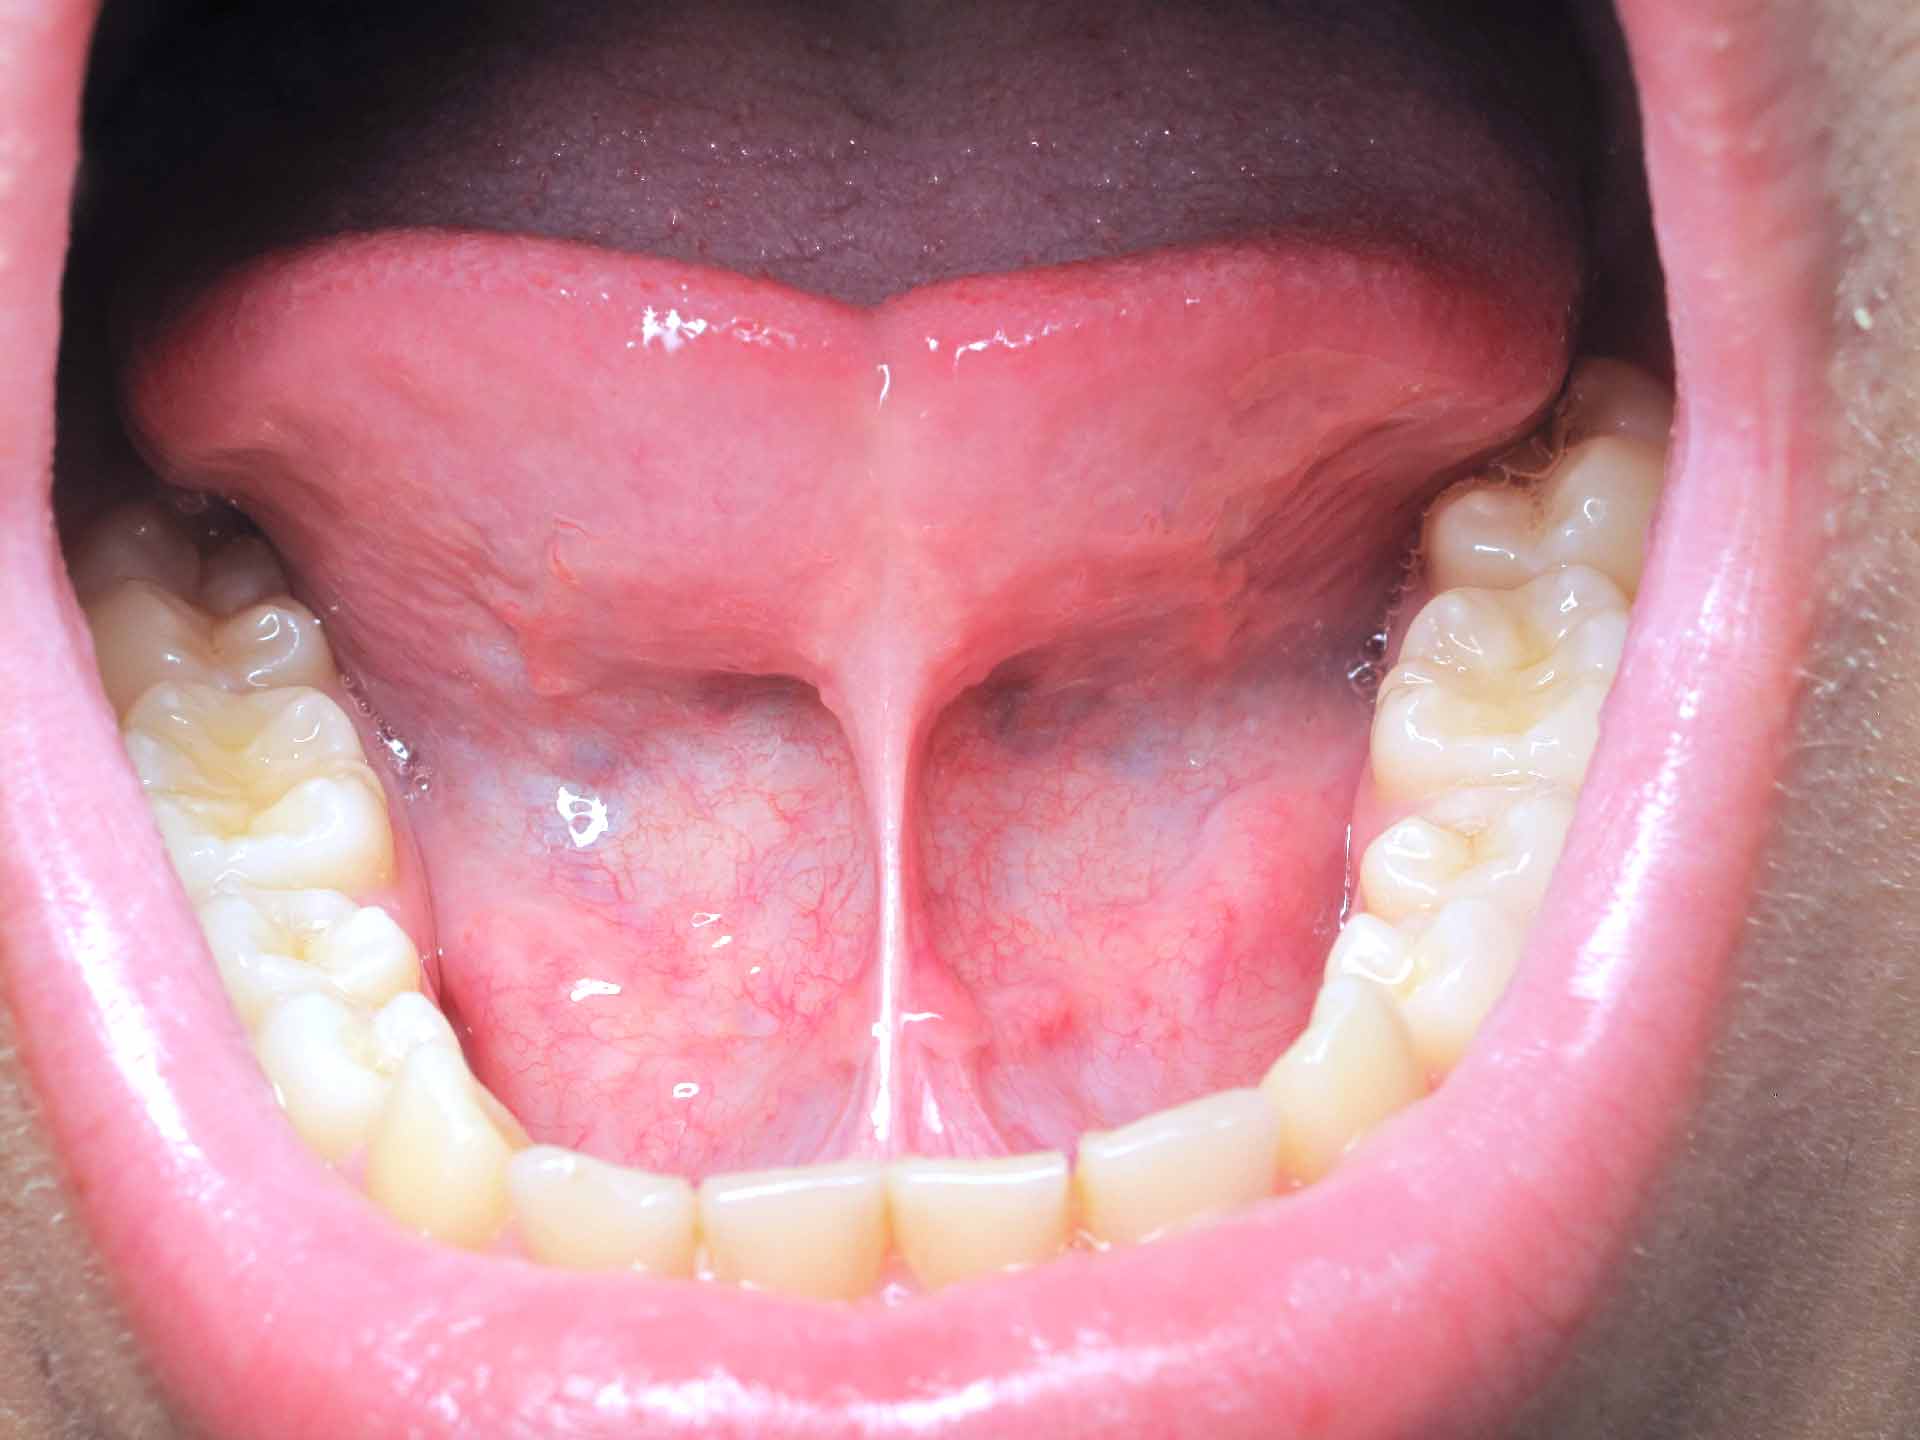

Laser frenulectomia

Lo studio dentistico Veloce&Palaia a Genova è specializzato in trattamenti di frenulectomia con laser. Un trattamento moderno e minimamente invasivo per correggere i problemi legati al frenulo labiale o linguale, che possono causare difficoltà nell’alimentazione, nel linguaggio o nelle funzioni orali quotidiane.

Utilizzando il laser, l’intervento è preciso e veloce, riducendo al minimo il dolore e il rischio di infezioni. I benefici includono una guarigione rapida, senza necessità di punti, e un miglioramento significativo nella mobilità della lingua o delle labbra, garantendo una qualità della vita migliore.